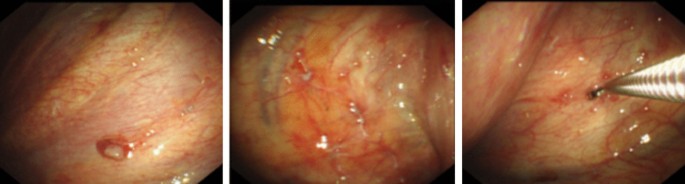

We report the case of a 32-year-old non-smoker female, who presented with mild dyspnea for two weeks. She denied cough, hemoptysis, fever and weight loss. Serologic tumor markers, including carcinoembryonic antigen (CEA) and α-fetoprotein (AFP), did not reveal any abnormalities. Tuberculin purified protein derivative (PPD) test of the patient was negative. A computed tomography scan (CT) of the chest revealed left pleural effusion, and there was no evidence of mediastinal lymphadenopathy and the lung fields were clear (Fig. 1a, b). Although undergoing repeatedly thoracentesis, the hemorrhagic pleural effusion was recurrent refilling. The routine biochemical test of pleural effusion showed that it was exudative, while no malignancy was detected on cytology examination. Thus, single port video-assisted thoracoscopy (VATS) was then performed. Thoracoscope showed a large number of nodules arising from the parietal pleura, with a tenacious texture and a clear margin. Biopsy was performed on multiple nodules, with a little bleeding (Fig. 2). Microscopic examination revealed the nodules comprised a conglomerate of capillary vessels, and some of the vascular spaces lined by proliferating endothelial cells. No significant atypia was found in the lining endothelial cells (Fig. 3a). Immunohistochemical (IHC) analysis showed CD31 and erythroblast transformation specific regulated gene-1(ERG) positive, and Ki-67 proliferation index was 2% (Fig. 3b–d). The biopsy was suggestive of capillary hemangioma. Dexamethasone (10 mg/day)was injected into the thoracic cavity for three consecutive days, and then the patient began to receive prednisone acetate (30 mg/day). Unfortunately, both topical and systemic dexamethasone were failure to control pleural effusion. The chest CT scan showed that medium-volume still exist after 4 weeks of oral corticosteroids (Fig. 1c, d). Hence, the patient stopped corticosteroids and switched to oral azathioprine 100 mg ever day. No side effect associated with azathioprine occurred. The patient was followed up regularly and the pleural effusion was gradually reduced. At the 12 months of follow up, reexamination with CT scan revealed no pleural effusion (Fig. 1e, f).

Diagnosis of hemangioma mainly depends on imaging and pathological examinations. Multifocal capillary hemangiomas may present numerous nodules on the pleural surface with pleural thickening on CT scan [9]. However, chest CT doesn’t always reveal findings suggestive of hemangiomas, especially those characterized by small pleural nodules. Medical thoracoscopy is an important method for the diagnosis of pleural hemangioma. Histopathological examination and IHC are essential. Microscopically, capillary hemangiomas consisted of vascular spaces lined by proliferating endothelial cells, with few dilated channels. The sparse inflammatory cells and fibrocollagenous stroma were found in the vascular spaces. The neoplasm showed no cellular atypia or mitosis [3, 10]. In our case, numerous nodules of pleura can found through thoracoscopy, which were biopsied and diagnosed as pleural capillary hemangioma.